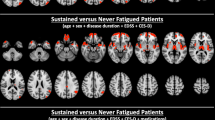

The Spearman correlations between study variables and fatigue level (no fatigue, mild to moderate fatigue, and high fatigue) are shown in Table 2. Positive correlations were found between age, disease duration, time to initiate DMT and relapse number (p = 0.034, 0.002, 0.028 and 0.009, respectively), while there was no association between gender and fatigue. There was also a significant positive correlation between EDSS and fatigue severity (p = 0.001). Significant positive associations between fatigue severity and both total and regional WM-LL were found. P values were 0.002 for total lesion volumes, 0.003 for periventricular lesion volume, 0.023 for juxtacortical lesion volume, and 0.003 for infratentorial lesion volume. This is also confirmed by using the raw data of FSS (Fig. 1).

Table 5 shows the results of multivariate logistic ordinal regression analysis (by forward stepwise method) using levels of Fatigue as the dependent variable. The model included disease duration, EDSS, time between onset to DMT, number of relapses, whole brain volume, juxta cortical lesion volume, periventricular lesion volume and infratentorial lesion volume. It was controlled for age, sex, and current DMT. Only EDSS and infratentorial lesion volume were identified as the best predictors, with p-values of 0.023 and 0.021, respectively.

Khedr and their colleagues10 found that fatigued MS patients had greater reduction in total brain volume, cerebral grey matter, and volumes of brain stem, thalamus, and caudate compared to non-fatigued patients. Regression analysis indicated that thalamic and brain stem atrophy are the best predictors of fatigue. Our study complements this by showing a significant relationship between infratentorial lesion volume and fatigue. Therefore, the best predictors of fatigue from both studies are thalamic and brain stem atrophy, as well as WM-LL of the infratentorial region (cerebellum and brain stem).

Our research revealed a significant relationship between the volume of infratentorial lesions and fatigue. After adjusting for age, gender, and current DMT, this association was maintained, but at a reduced strength. As far as we know this has not been reported in many previous studies. A recent study found that selective cerebellar pathology could potentially play a role in the development of fatigue and depression in RRMS, which in turn may exacerbate disability in these individuals.34 Since the cerebellum plays a critical role in action control and motor learning, and its non-motor activities are gaining recognition35, it may well contribute to the sense of fatigue.

To the best of our knowledge, limited research has been conducted to elucidate the structural alterations in the brain associated with fatigue in multiple sclerosis (MS) patients. In a prior study by Khedr et al., we quantified brain volumetric changes in fatigued and non-fatigued individuals with relapsing–remitting MS (RRMS) and identified that atrophy of the thalamus and brain stem exhibited the strongest predictive value for fatigue10. Another study by Riccitelli et al. employed a comprehensive voxel-wise analysis of the entire brain to examine the regional distribution patterns of lesions and revealed atrophy in the left central sulcus and precentral gyrus (primary sensory motor area) among fatigued patients39. Moreover, previous research by Cruz Gómez et al. and Damasceno et al., has established a correlation between cerebellar volume reduction, brain stem volume loss, and fatigue in MS40,41. In the present study, we specifically observed a significant association between infratentorial lesion volume load and fatigue, highlighting infratentorial lesion load as the most reliable predictor of fatigue. This could be explained as cortical gray matter atrophy, as well as cerebellar and brain stem lesions, which may impede efficient motor and sensory information processing between cortical areas and cerebellar/brain stem regions, ultimately leading to the manifestation of fatigue40.